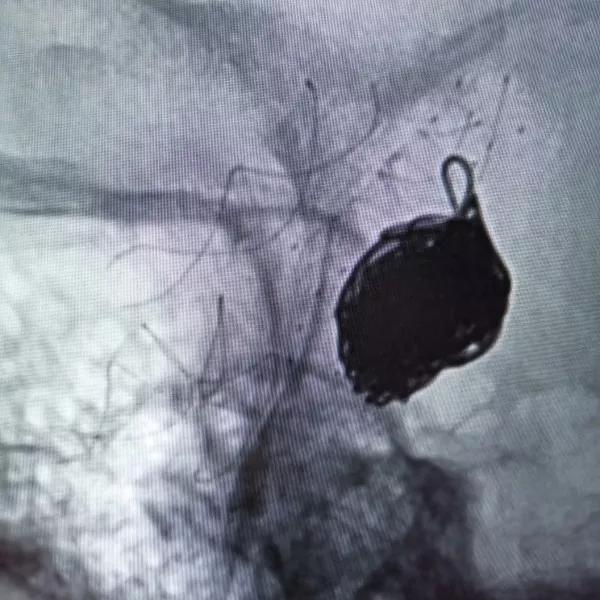

选择4.0×15mm Tubridge®支架,成功释放,覆盖颈内动脉床突上段动脉瘤。

▲各角度观察显示Tubridge®贴壁良好

▲造影见造影剂滞留,载瘤动脉通畅。